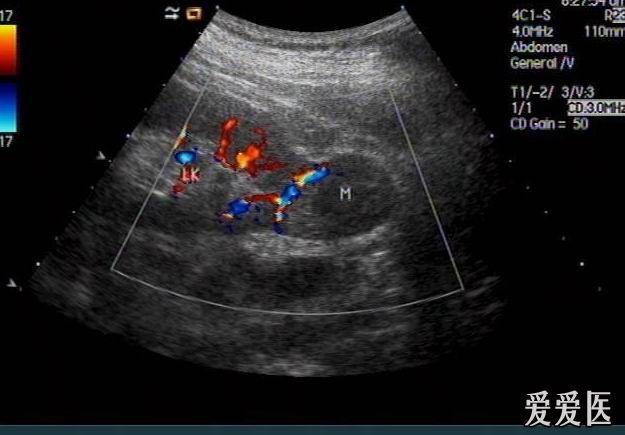

肾肿瘤彩超

肾肿瘤彩超,肾肿瘤ct

肾肿瘤超声鉴别诊断

肾结核?肾肿瘤?

体检时超声要尽量防止漏诊肾癌